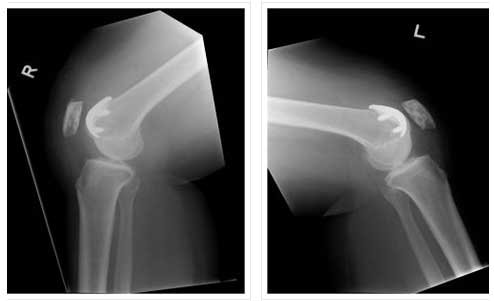

BILATERAL PATELLOFEMORAL REPLACEMENT

BILATERAL PATELLOFEMORAL REPLACEMENT

LATERAL VIEW

Right medial and left bicomp

Right UKA, Left bicomp